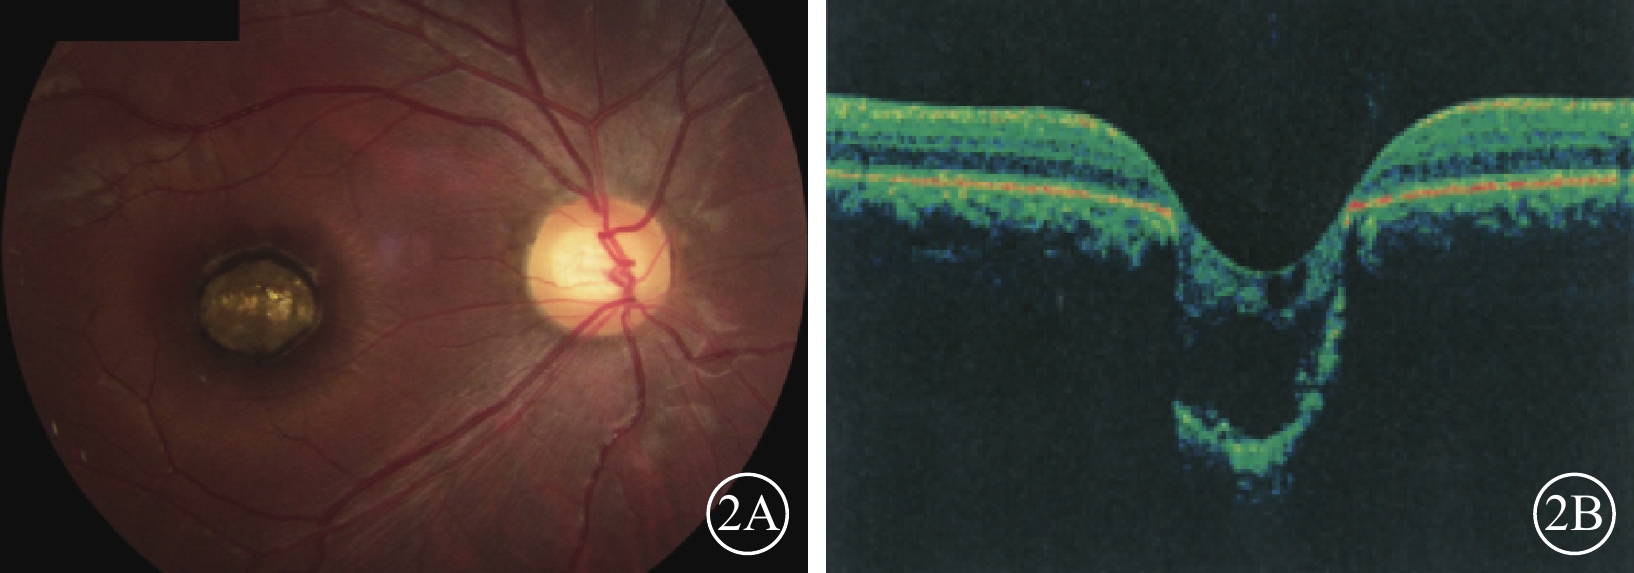

圖2

例2患者右眼彩色眼底、OCT像。2A. 彩色眼底像,黃斑區可見一大小約1.0 DD的邊界清晰的橢圓形缺損;2B. OCT像,病灶區視網膜脈絡膜組織隨鞏膜組織向外凹陷,凹陷區域內視網膜神經上皮層薄變及缺損,神經上皮層間呈囊樣變化伴淺脫離

圖2

例2患者右眼彩色眼底、OCT像。2A. 彩色眼底像,黃斑區可見一大小約1.0 DD的邊界清晰的橢圓形缺損;2B. OCT像,病灶區視網膜脈絡膜組織隨鞏膜組織向外凹陷,凹陷區域內視網膜神經上皮層薄變及缺損,神經上皮層間呈囊樣變化伴淺脫離

例2 例1之兄,29歲。因自幼雙眼視力差與例1同時來我院就診。眼科檢查,雙眼眼位正位,無眼球震顫。右眼視力0.1,?7.50 DS/+4.00 DC×90°=0.1;左眼視力0.05,?4.00 DS/+3.00 DC×85°=0.1。右眼眼壓19 mmHg,左眼眼壓20 mmHg。雙眼瞳孔對光反射遲鈍,其余眼前節檢查正常。雙眼視盤邊界清楚,顏色基本正常,C/D=0.3;視網膜平復,黃斑區可見約1.0 DD大小的類圓形缺損區(圖2A);其邊界清晰,凹陷深,中間可見灰白色鞏膜組織,脈絡膜毛細血管缺失。OCT檢查,雙眼黃斑缺損區視網膜脈絡膜組織隨鞏膜組織局限性向外凹陷,凹陷區域內視網膜神經上皮層變薄,部分缺損,神經上皮層間囊樣改變,其下見淺脫離(圖2B)。基因檢查:患者攜帶下列雜合突變:(1)CEP290 c. 3573+3A>G;(2)CEP290 c. 366A>G,p. K122K。診斷:雙眼先天性黃斑缺損(色素型)。

圖2

例2患者右眼彩色眼底、OCT像。2A. 彩色眼底像,黃斑區可見一大小約1.0 DD的邊界清晰的橢圓形缺損;2B. OCT像,病灶區視網膜脈絡膜組織隨鞏膜組織向外凹陷,凹陷區域內視網膜神經上皮層薄變及缺損,神經上皮層間呈囊樣變化伴淺脫離

圖2

例2患者右眼彩色眼底、OCT像。2A. 彩色眼底像,黃斑區可見一大小約1.0 DD的邊界清晰的橢圓形缺損;2B. OCT像,病灶區視網膜脈絡膜組織隨鞏膜組織向外凹陷,凹陷區域內視網膜神經上皮層薄變及缺損,神經上皮層間呈囊樣變化伴淺脫離

例2 例1之兄,29歲。因自幼雙眼視力差與例1同時來我院就診。眼科檢查,雙眼眼位正位,無眼球震顫。右眼視力0.1,?7.50 DS/+4.00 DC×90°=0.1;左眼視力0.05,?4.00 DS/+3.00 DC×85°=0.1。右眼眼壓19 mmHg,左眼眼壓20 mmHg。雙眼瞳孔對光反射遲鈍,其余眼前節檢查正常。雙眼視盤邊界清楚,顏色基本正常,C/D=0.3;視網膜平復,黃斑區可見約1.0 DD大小的類圓形缺損區(圖2A);其邊界清晰,凹陷深,中間可見灰白色鞏膜組織,脈絡膜毛細血管缺失。OCT檢查,雙眼黃斑缺損區視網膜脈絡膜組織隨鞏膜組織局限性向外凹陷,凹陷區域內視網膜神經上皮層變薄,部分缺損,神經上皮層間囊樣改變,其下見淺脫離(圖2B)。基因檢查:患者攜帶下列雜合突變:(1)CEP290 c. 3573+3A>G;(2)CEP290 c. 366A>G,p. K122K。診斷:雙眼先天性黃斑缺損(色素型)。